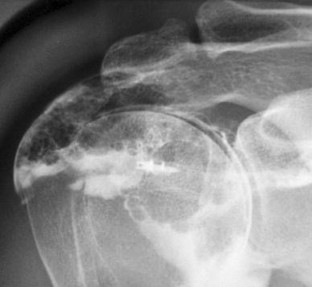

Fig. 2